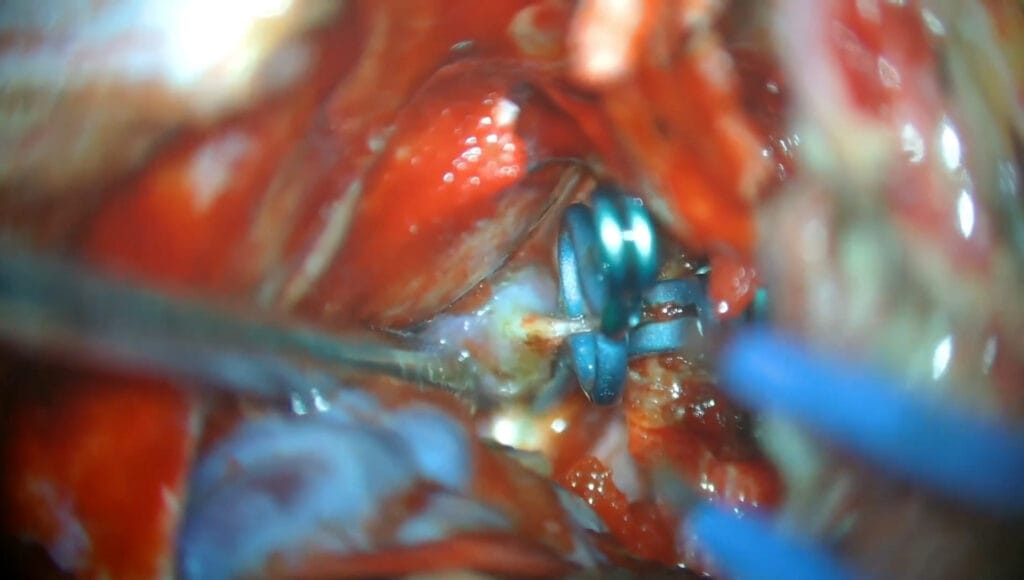

Clipaje transcavernoso de aneurisma de la ACS

Se presenta un caso de clipaje de un aneurisma de la arteria cerebelosa superior con un tratamiento previo con flow-diverter fallido.